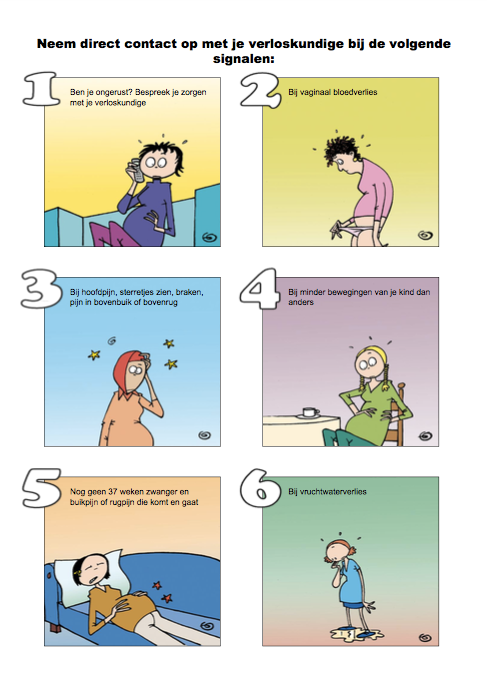

0-40 weken zwanger

Signalenkaart

Bij onderstaande klachten moet je contact met ons opnemen!!!!!!!!!!!!!!!!!!!